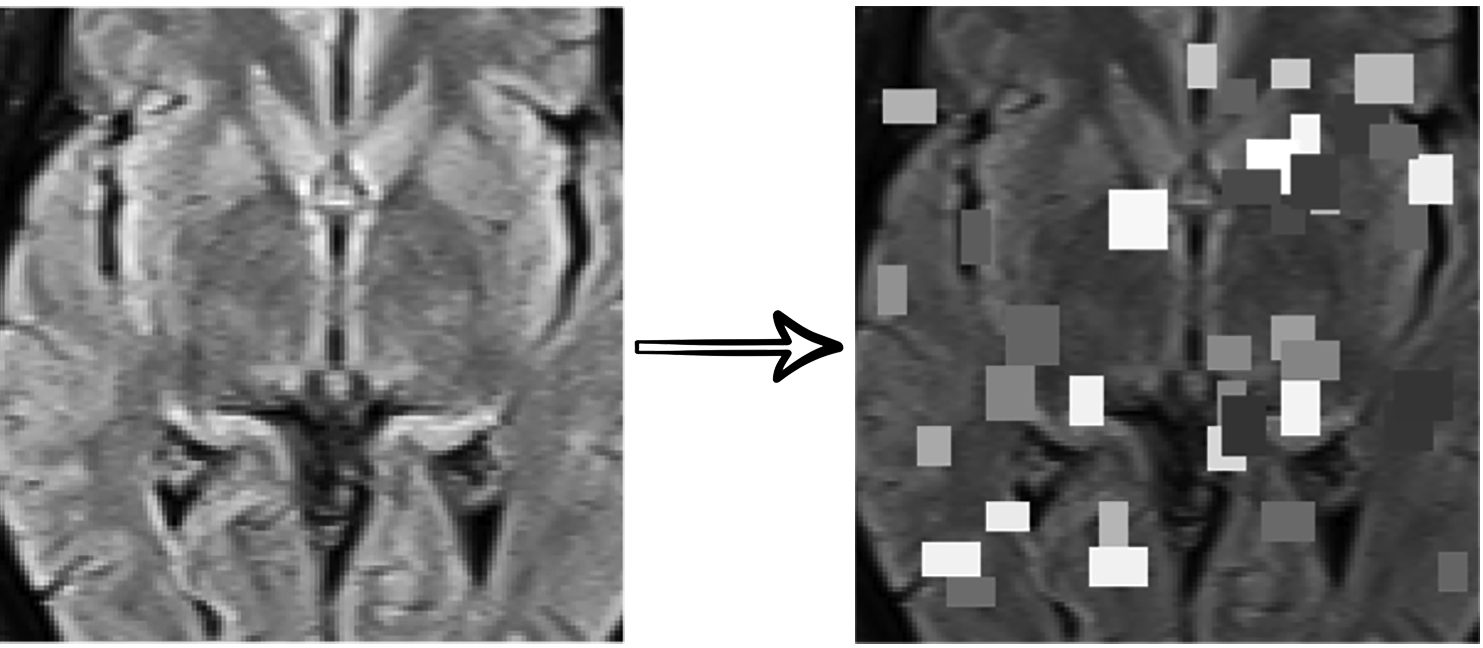

In this work, we use a self-supervised learning method to extract specific features of our data from multiple perspectives (appearance, texture, context, etc.) by combining three different supervision tasks that were proposed in “Models Genesis” [31]. Our model consists of a U-Net [25] with a ResNet [9] encoder. Each supervision task consists of a particular transformation and reconstructing the original image from the transformed one (see Fig. 3). Finally, the encoder part of the network is fine-tuned for the target classification task.

Refer to caption

(a) Non-linear transformation

(b) Local shuffling

(c) In-painting

(d) Out-painting

Figure 3: Self-supervised transformations: (a) Non-linear Intensity Transformation enforces the model to learn the shape and intensity distribution as the appearance of organs.(b) Local Pixel Shuffling enforces the model to learn local boundaries as the texture of organs. (c,d) Out-painting and In-painting enforces the model to learn geometry and spatial layout of organs via extrapolating and local continuities of organs via interpolating as the context of images, respectively.